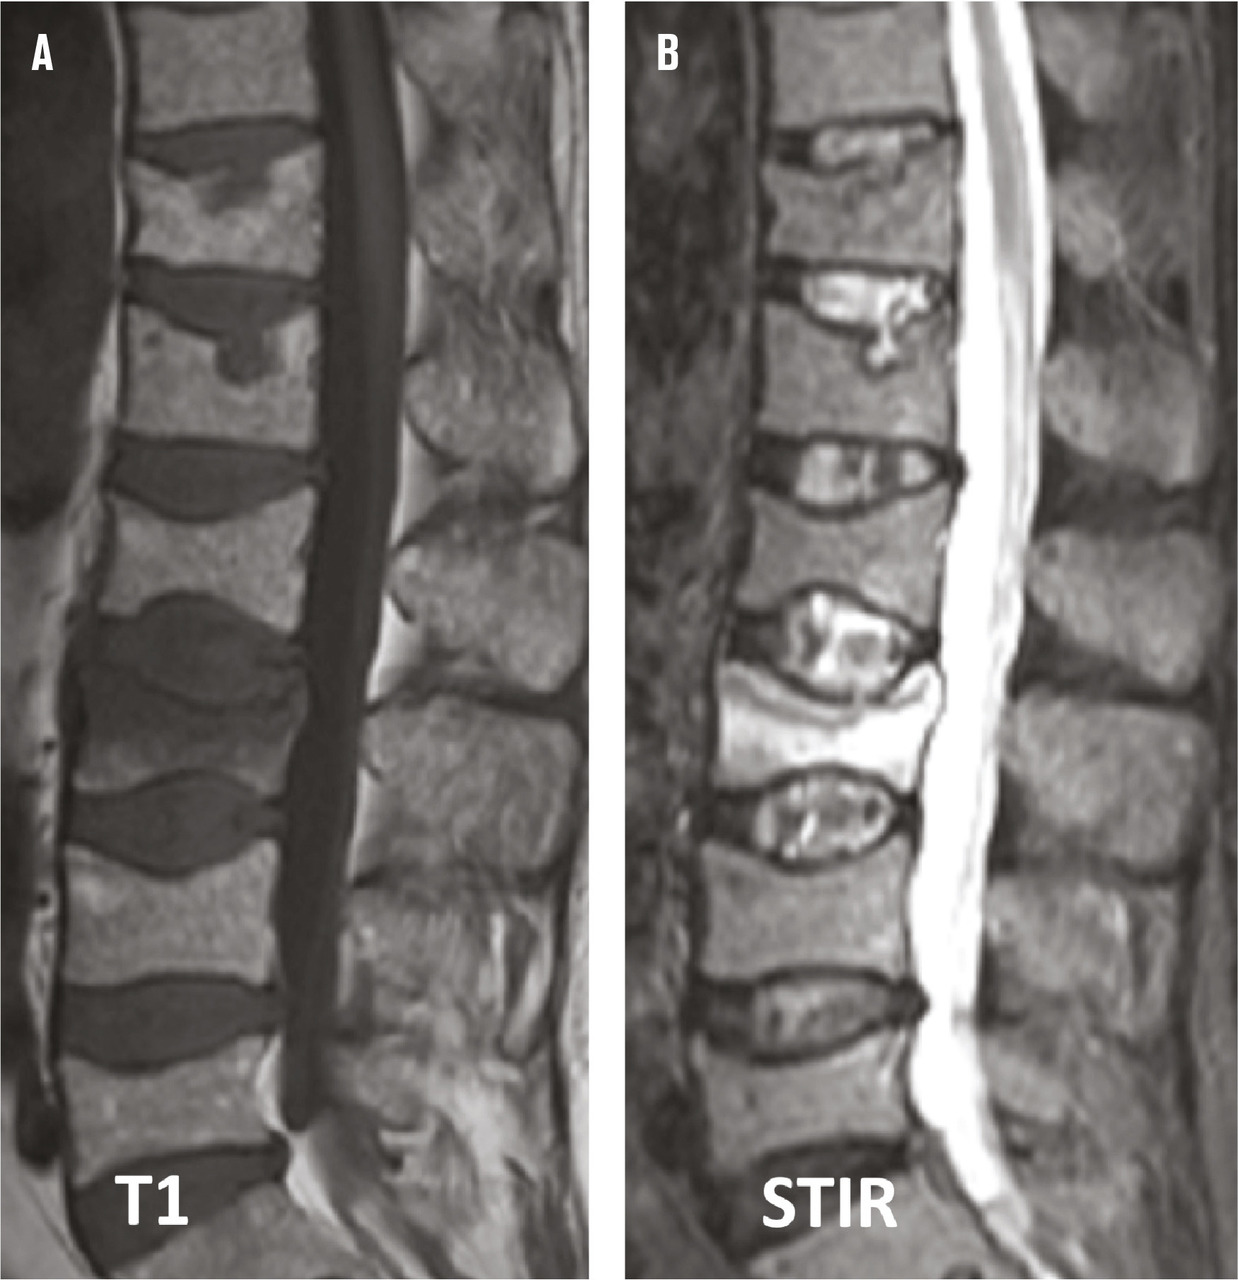

Une première explication à la négativité de ces essais randomisés est l’importance de l’effet placebo sur une douleur d’une procédure factice dont la mise en scène est en tout point similaire à celle d’une véritable intervention. Ces deux essais contrôlés ont aussi un certain nombre de limites méthodologiques. Une proportion importante des patients avait des douleurs depuis plus de 3 mois : inclure des patients jusqu’à un an après la survenue de leur fracture vertébrale ostéoporotique va à l’encontre du bon sens clinique, d’autant que les garanties apportées par les auteurs sur la relation entre la fracture et les douleurs persistantes sont insuffisantes. Ces essais comportent aussi des limites d’ordre technique : le trocart était de faible calibre, l’abord unipédiculaire et par conséquent la quantité de ciment injectée dans les corps vertébraux relativement faible. Deux limites majeures de ces études sont à souligner. L’intensité douloureuse requise pour pouvoir inclure ces patients était très modérée puisque le seuil minimal sur une échelle d’auto-évaluation (échelle visuelle analogique [EVA]) requis comme critère d’inclusion n’était que de 3 ou 4 sur 10,4, 3 ce qui est défavorable à la mise en évidence de tout effet thérapeutique. Enfin et surtout, les patients étaient inclus sans s’être formellement assurés de la présence d’un signal d’œdème médullaire en imagerie par résonance magnétique (IRM), critère majeur de définition du caractère récent d’une fracture vertébrale ostéoporotique et de sa responsabilité dans les douleurs vertébrales (fig. 3).

Dans la majorité des cas, les douleurs directement en rapport avec la fracture s’amendent en quelques semaines avec la consolidation du foyer de fracture. Cependant, la déformation induite par la fracture peut déclencher des douleurs articulaires, ligamentaires ou musculaires. Il faut bien avoir à l’esprit cette cause potentielle statique de douleurs, notamment quand celles-ci durent au-delà de 6 à 8 semaines alors que le tassement ne s’est pas majoré entre-temps et que l’« œdème » médullaire de la vertèbre fracturée s’est résorbé en IRM. Il est de bonne règle, quand la fracture n’est plus récente ou que l’œdème visualisé sur l’IRM est peu marqué, de commencer par une infiltration de dérivés cortisoniques dans les articulations postérieures qui peuvent être responsables des douleurs persistantes.